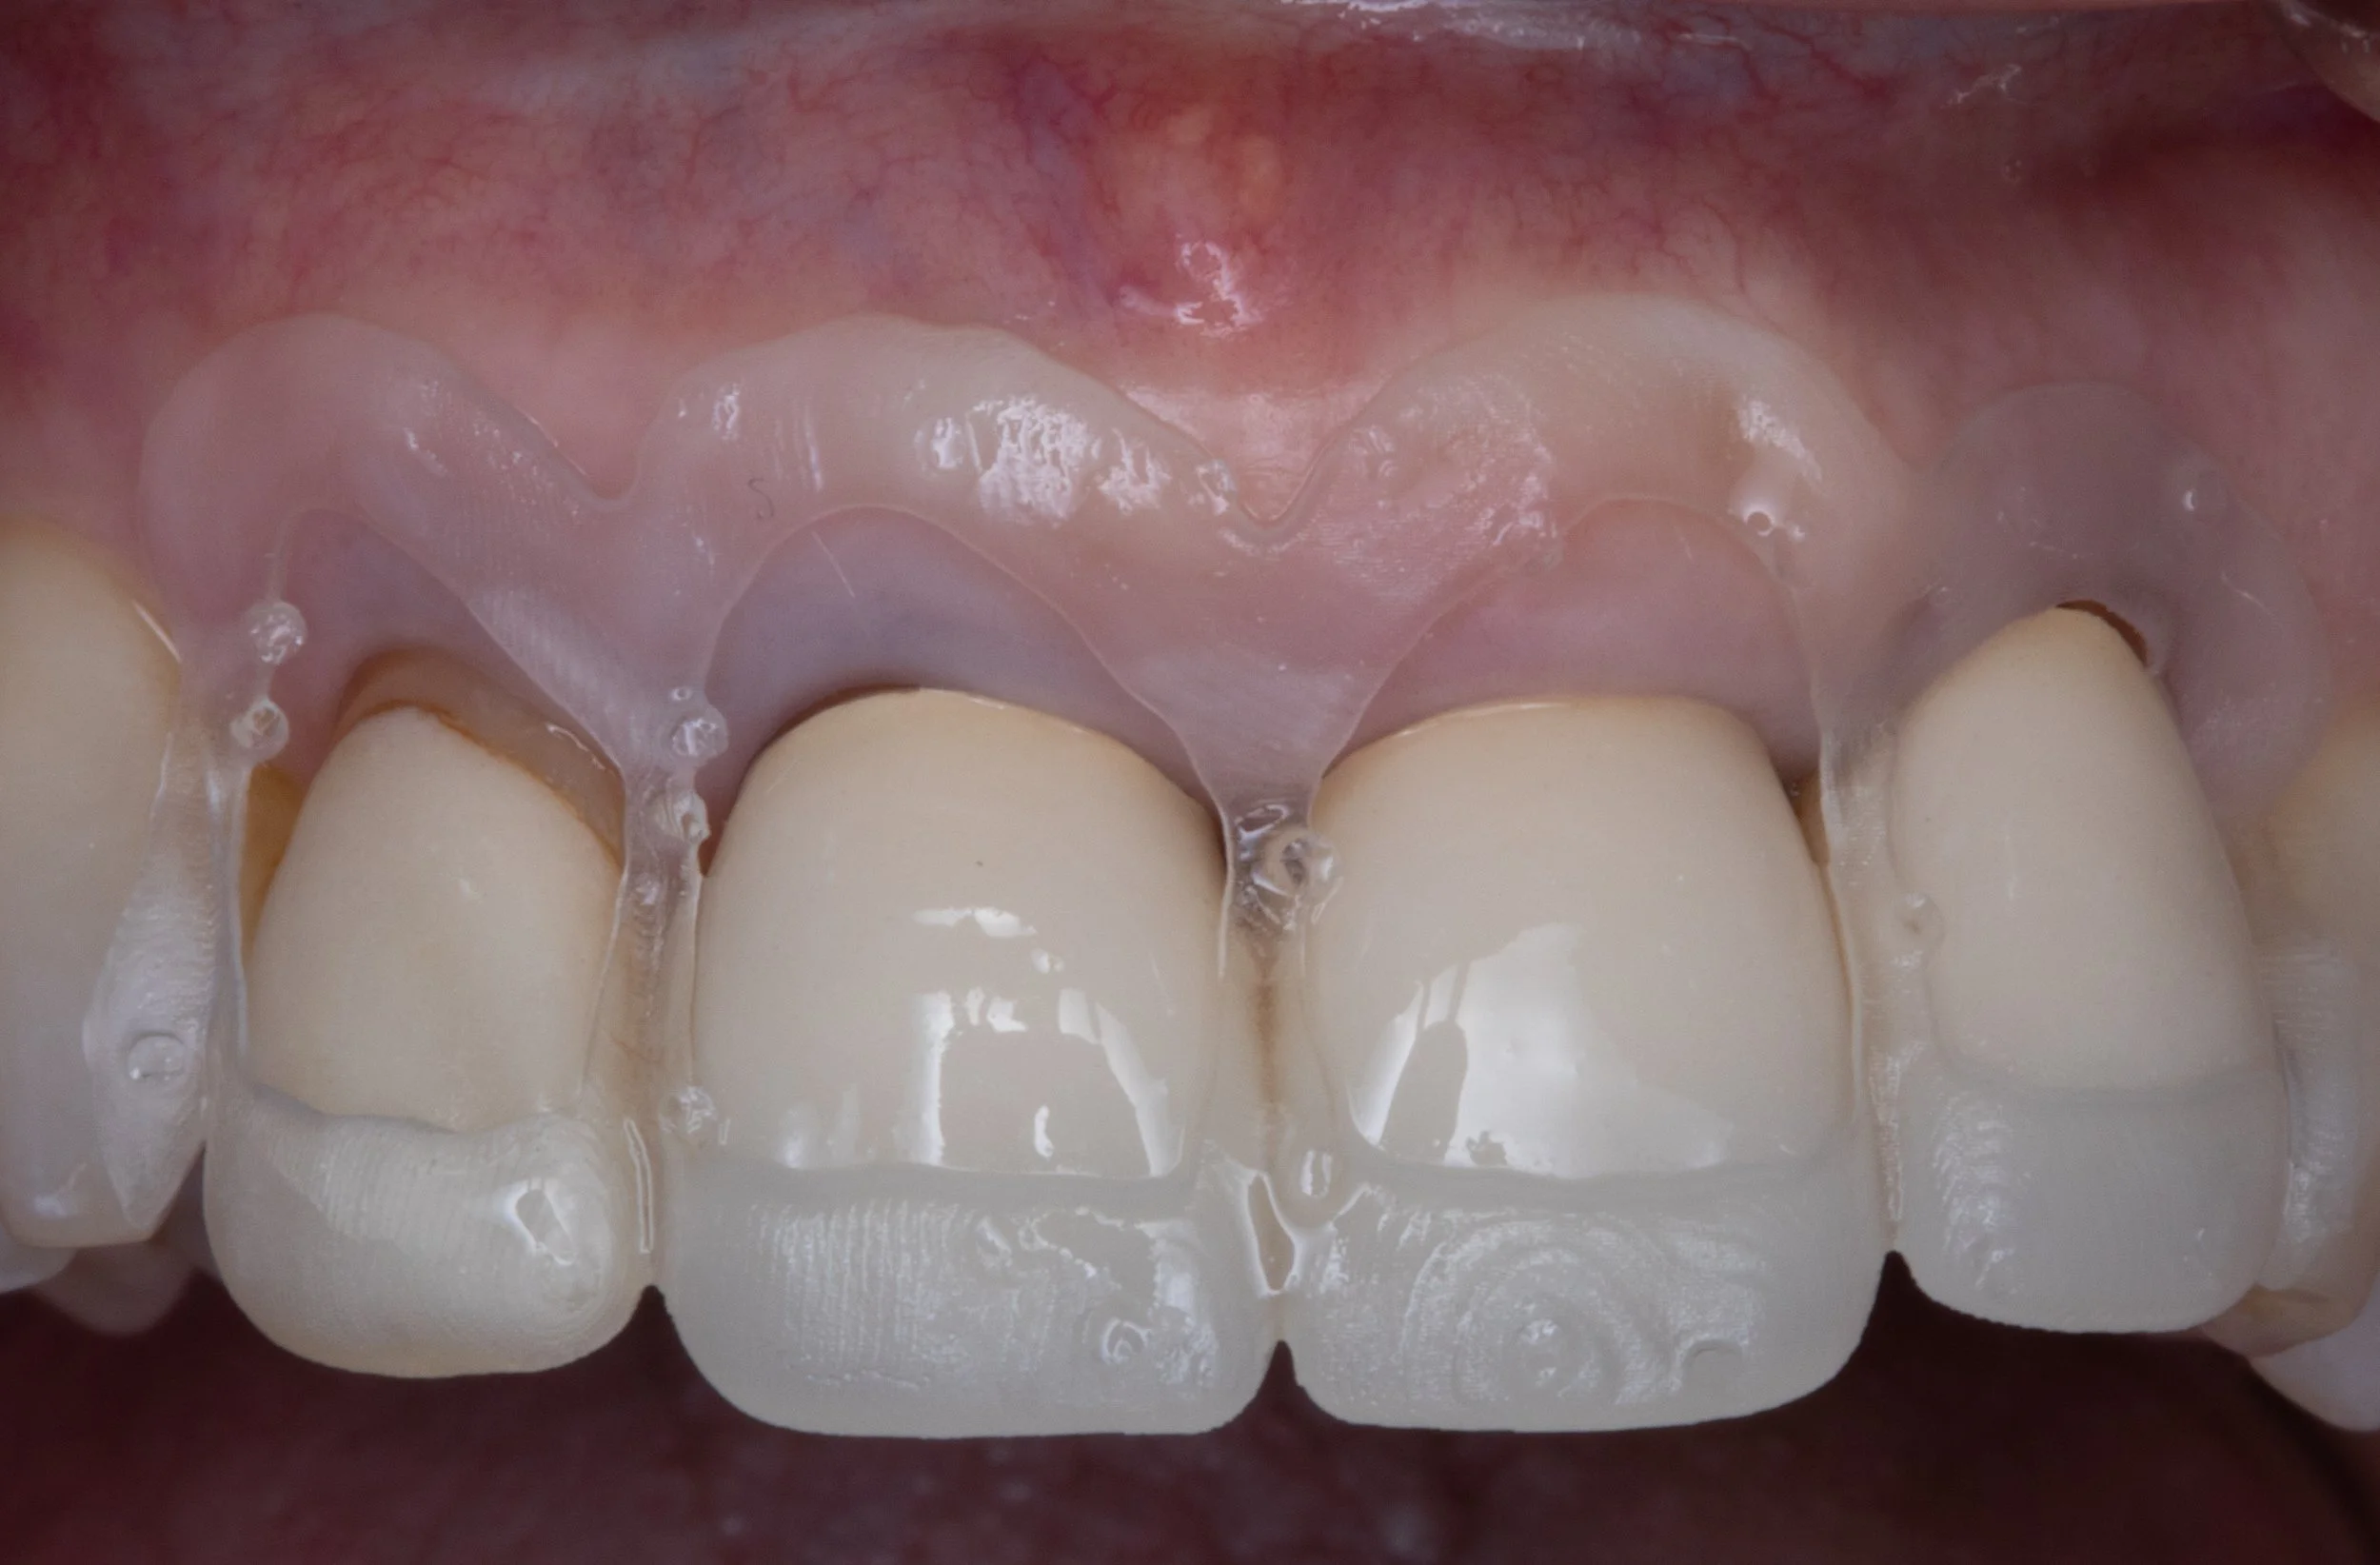

This procedure may be recommended by your dentist in order to expose more tooth structure before placing a crown. In some patients, it may be recommended for patients with excessive gum display when they smile.